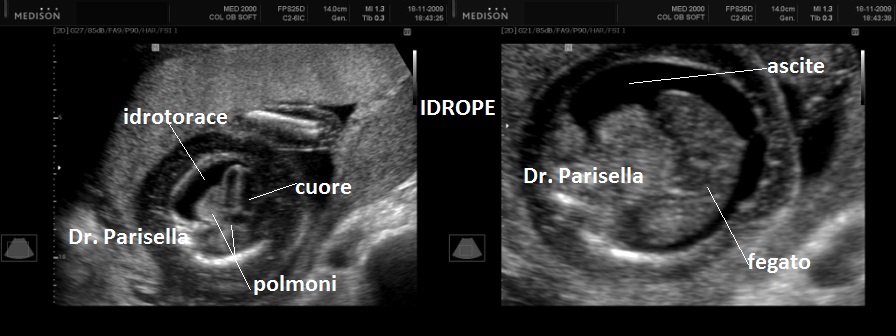

La Diagnosi Prenatale Ecografica si basa su:

3) Idrope.